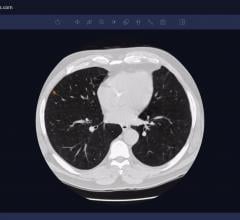

March 31, 2020 — The Intelligent Evaluation System of chest computed tomography (CT) for COVID-19, developed by YITU ...

March 20, 2020 — An artificial intelligence deep learning model can accurately detect COVID-19 and differentiate it from ...